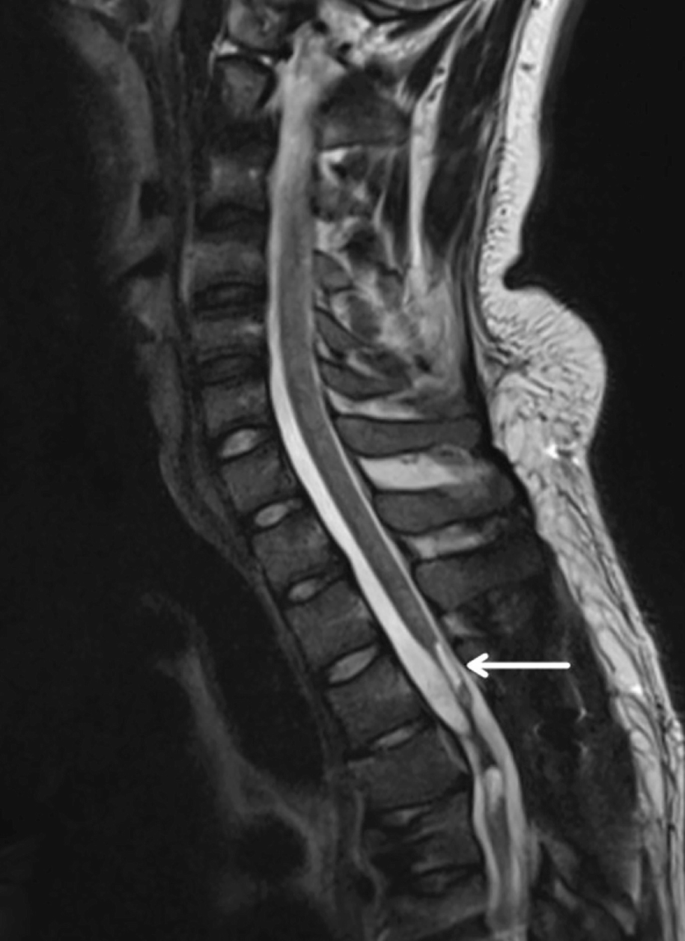

創傷性脊髓損傷是由于脊柱受到突然的強力撞擊,導致椎骨骨折、脫臼、擠壓或壓縮(圖1)。主要原因包括機動車事故,其中汽車和摩托車碰撞占每年新增脊髓損傷病例的近一半。跌倒,尤其是65歲及以上人群的跌倒,是造成脊髓損傷的重要原因,約占60%。體育活動,例如沖擊性運動和淺水潛水,約占此類損傷的10%。

慢性期開始于損傷后約3-6個月,并持續患者的余生,典型特征是囊腫形成和嚴重的神經膠質瘢痕(圖2)。